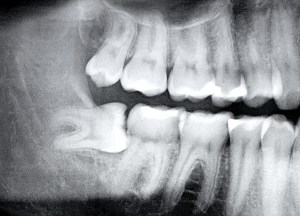

But still almost all of us have them. Scientists believe this third set of molars was important when our diet involved stuff like leaves and roots (I’m guessing not the buttery mashed potato kind) and we needed more chewing power. And since our jaws have become smaller but the wisdom teeth keep on coming, there is no room for them. So they get impacted, i.e. blocked by other teeth.

Back to wisdom teeth, my major question was why they are considered wise, since they clearly are not. That answer is a little underwhelming, I’ll warn you: Because you develop these chompers later than the rest of your teeth, you are considered to have more wisdom by the time they emerge. Usually they start forming around the age of 10 and “erupt” (yes, that’s the term) when you’re between 17 and 25. Honestly, if you ask me, we need to get a way cooler explanation.